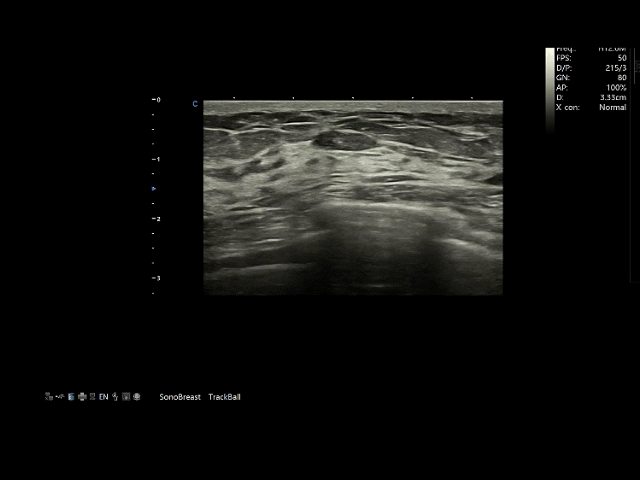

SonoBreast基于深度学习算法,通过对海量标注的乳腺超声影像数据进行学习,可以精准识别从形态、边界到血流信号的多维度特征,实现从“看图像”到“析病灶”的认知升级。它能敏锐捕捉毫米级微小病灶与钙化点,并依据国际BI-RADS标准进行评估与分级,以可视化界面为医生提供客观、量化的决策支持,有效弥补因经验不足或疲劳带来的诊断差异,显著提升诊断的一致性。

在效率层面,SonoBreast将传统手动测量所需的十余个步骤简化为秒级自动完成,极大解放了医生生产力,优化了诊疗流程。更深层的价值在于,它逐渐成为提升整体医疗服务质量的关键工具。在优质医疗资源分布不均的现状下,该软件能有效赋能基层医院,通过提供标准化的分析支持,帮助年轻医生快速提升诊断能力,缩小不同层级医疗机构间的诊疗水平差距,让更多的女性都能享受到精准、便捷的乳腺健康筛查服务。